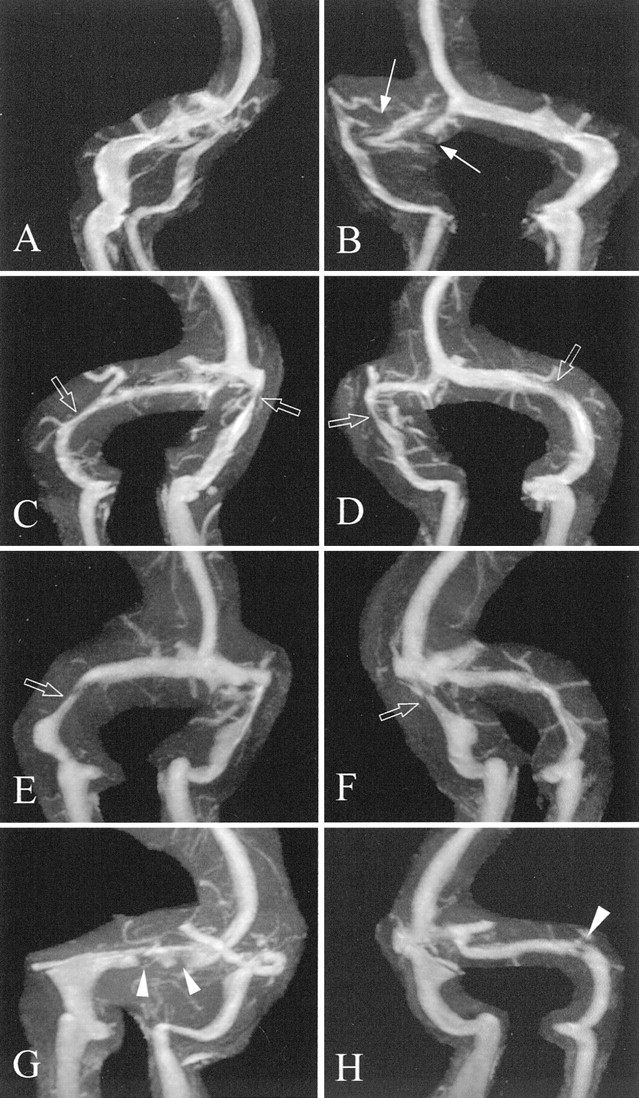

图3。Auto-triggered elliptic-centric-ordered三维gadolinium-enhanced先生造影术发现颅内高压症患者。老挝和饶分段最大强度投影(A和B)病人77;(C和D)病人36;和(E和F)病人8。(A)不连续(得分= 0)被认为在右侧横窦(箭头)(B)。extralumenal压狭窄的例子(打开箭头)在(B-F)。经管障碍物的例子被认为双边(箭头)病人69 (G和H)。